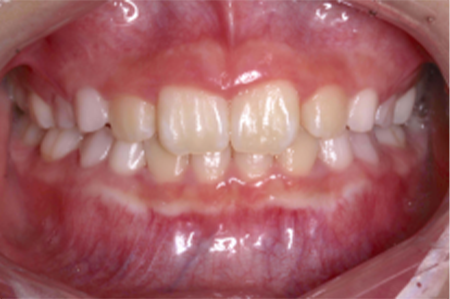

| 治療の経緯 | お母さまが子供の前歯の歯並びが気になるとのことで来院。 |

| 治療方法 | 右上2番が内側に入り込んでいる、部分的な反対咬合でしたので、 永久歯にだけ矯正装置をつけ、ワイヤーの力で、歯並びを改善しました。 |

| 治療期間 | 8ヵ月 |

|---|---|

| 費用 | インプラント 37万円×2本 骨造成 15万円 インプラント補綴 メタルボンド 15万円 |